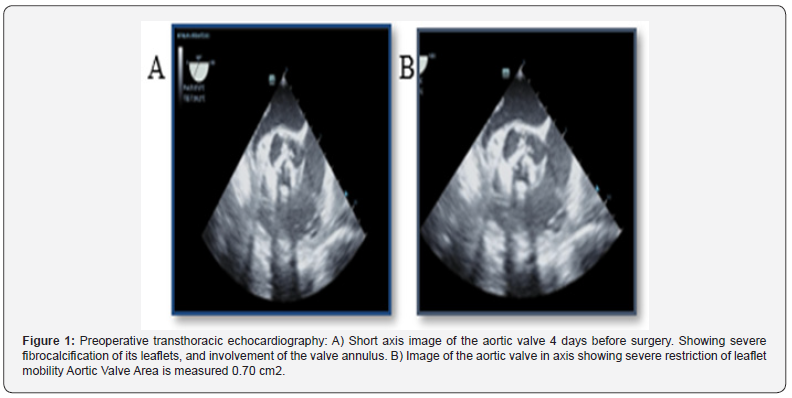

This is the case of a 53-year-old man admitted to the hospital’s emergency department with heart failure associated with aortic valve disease. Past medical history revealed previous hospitalization for Hyperuricemia with crisis and respiratory symptoms, although these have not been well clarified. To determine the etiology, a preoperative transthoracic echocardiogram was performed and showed a left ventricular ejection fraction (LVEF) of 66%, moderate concentric hypertrophy of the left ventricular wall and mild systolic dysfunction. The results of the aortic valve were as follows: Significant fibro calcification of its leaflets, which generates an important limitation in its opening and moderate incompetence in its closure. Aortic valve area 0.70 cm2.

a) Stenosis gradient: maximum pressure gradient 84.8 mmHg, mean pressure gradient 55 mmHg. Double aortic lesion with a predominance of significant aortic stenosis, aortic annulus - 23.5 mm of undefined etiology, due to the presence of significant fibro calcification that compromised the entire valve apparatus. The left ventricular tip diastolic and systolic diameters were 53 mm and 34 mm, respectively. The thicknesses of the interventricular septum and posterior left ventricular wall were 16 mm and 14 mm.

b) Other Tests Performed: Hemoglobin 13 g/dL, hematocrit 38.8%, white blood cells: 5,700 u/L, Neutr: 58.1%. Platelets: 196 u/L, Clucose: 90 mg/dL, Urea: 36 mg/dL, Creatinine: 0.6 mg/dL, Troponin T 0.024 ug/L, Uric Acid 8.0 mg/dL, C-Reactive Protein 0.839 mg/L dL. Transpercutaneous coronary angiography (PTCA) without coronary lesions (Figure 1).